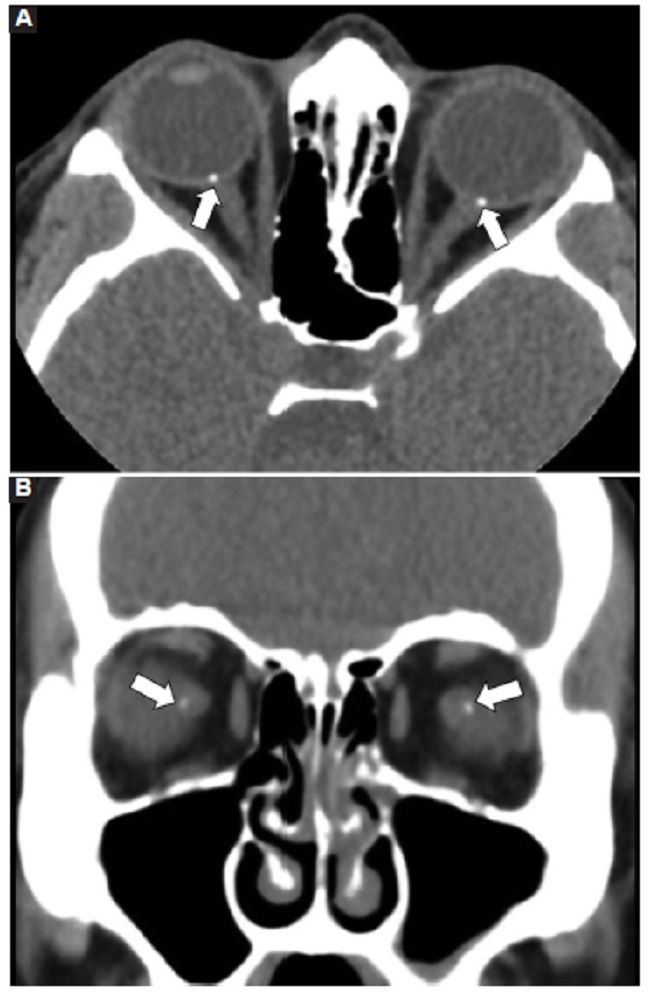

Las calcificaciones oculares y el material médico se pueden confundir con cuerpos extraños u otras lesiones orbitarias1. Las localizaciones típicas de las calcificaciones permiten diferenciarlas de cuerpos extraños hiperdensos. Las más frecuentes son las calcificaciones trocleares, las placas esclerales, las drusas del nervio óptico y la ptisis bulbi. Las primeras tienen localización superomedial dentro de la órbita (Fig. 13), en la tróclea del músculo oblicuo superior, aunque se pueden observar en todas las edades, hay mayor prevalencia de calcificaciones trocleares en pacientes con enfermedades autoinmunes y niveles elevados de fosfatasas alcalinas. Las placas esclerales se localizan en los sitios de inserción de los músculos rectos medial y lateral (Fig. 14) y son más comunes en los pacientes ancianos. Las calcificaciones que ocurren cerca del disco óptico se conocen como drusas del nervio óptico (Fig. 15), las cuales se asocian a degeneración macular y pueden ser causa de pseudopapiledema benigno. La ptisis bulbi es una atrofia y calcificación del globo ocular como secuela de enfermedades infecciosas, inflamatorias o traumáticas previas (Fig. 16) (1,11. Los imitadores de lesiones abiertas del globo ocular incluyen las deformidades como coloboma, estafiloma y el globo ocular elongado por glaucoma o miopía (Fig. 17). Las masas orbitarias y los hematomas también pueden alterar el contorno del globo ocular y asociarse a calcificaciones o relacionarse con desprendimiento de retina (Fig. 18) (1,6,8,11.